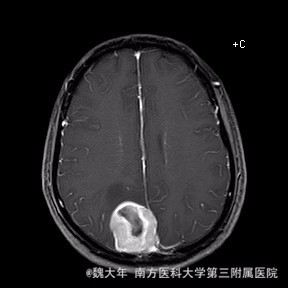

52岁,女性,因“反复头痛10余年,加重1年”入院。患者10余年前无明显诱因始出现头痛,表现为全头发作性胀痛,反复发作,无伴头晕、恶心,无呕吐、肢体抽搐,自行服药(具体不详)及休息后缓解,未予特殊处理。1年前患者觉头痛逐渐加重,以右顶部为甚,劳累或日晒后加重,无头晕、视物旋转,无恶心、呕吐,无发热、寒战,休息或平躺后症状稍有缓解,自行服药不能改善,至当地医院就诊,查颅脑MRI和CT提示“右侧顶部脑膜瘤”。

行“右顶开颅右顶部矢状窦旁脑膜瘤切除术”。取右顶马蹄形手术切口 ,颞侧翻开皮瓣,电刀切开骨膜,中线矢状缝上前、后极各钻一孔,颞侧后方钻一孔,铣刀铣一长方形(7*6cm)骨瓣,见硬膜表面较多点状渗血,予充分止血,悬吊硬膜。 显微镜下切除肿瘤:沿肿瘤边缘剪开硬膜后,见一大小约5*5*6cm肿瘤,沿硬膜内侧面呈匍匐状生长,边界与脑组织有蛛网膜分隔,质地较韧,基底与矢状窦关系密切,靠内侧与大脑镰粘连紧密,血供丰富。仔细分离肿瘤与脑组织的粘连,全切除肿瘤。肿瘤基底与矢窦粘连紧密,并破坏矢状窦侧壁,予低功率电刀反复烧灼,直至肿瘤无明显血供表现。严密止血后常规关颅。

术后1周复查头颅MR未见明显肿瘤残留,拆线后出院。